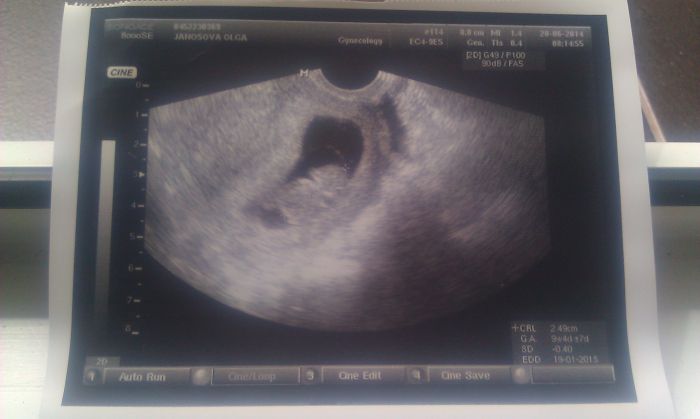

[571993]Olie,to je krásný obrázek

To je z dnešní kontroly?

[572019]ano z dnesni kontroly, miminko krasne roste, uz mame 2,49cm

[572028].....to je dobře,že mimísek prospívá. Olie,ty jsi v devátém týdnu? Docela ti závidím,já jdu až 14.7 a to už budu 12+2tt a hned další den jdu na genetiku

dneska jsem 9+5, pristi tyden jdu na krev do gennetu do Prahy, 4.7 na krev na gyndu, 10.7 na screening a 11.7 zase na gyndu.